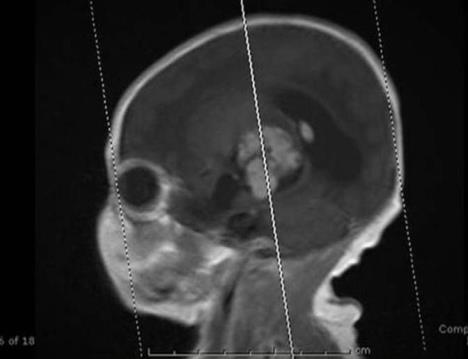

Ali kako je stigla u kasnije faze trudnoće, doktori su pronašli nešto zabrinjavajuće: Beba je navodno imala tumor na mozgu. Oni su savetovali Tifni da se ubrza porođaj i ona se složila. Čim je beba bila rođena, hitno su je odveli na operaciju.

Tokom operacije, doktor Greb video je nešto što nikada ranij enije video: stopalo, potpuno formirano u pacijentovom mozgu.

"To me je nateralo da zaustavim operaciju, jer nisam baš navikao da vidim stopalo u mozgu", rekao je kasnije Greb.

Stopalo je najverovatnije bilo teratoma, što je zapravo masa koja se stvara tokom trudnoće sa nekompletnim delovima tela. Moguće je i da je bio "fetus unutar fetus", neobično stanje u kome blizanac počne da raste u drugom.